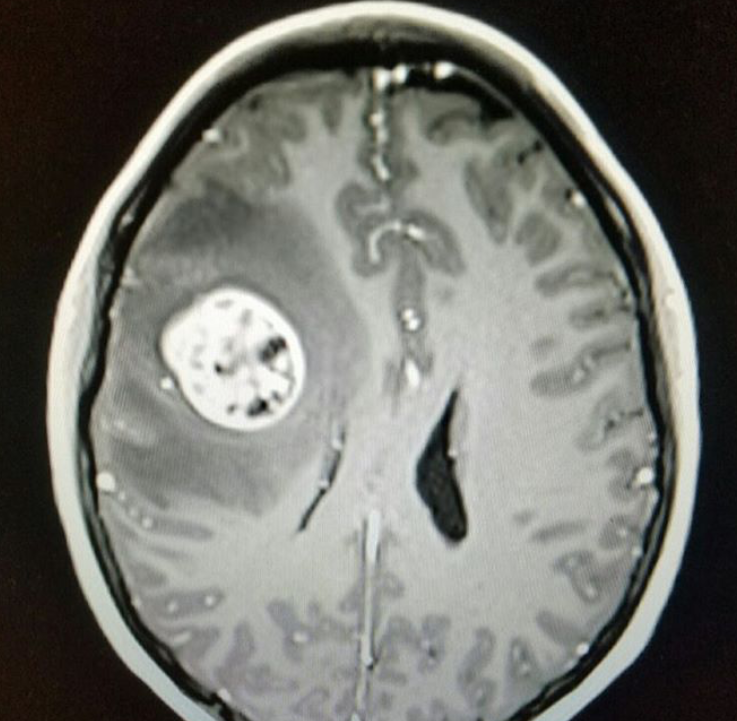

Four days before Christmas this year Lisa was given life shattering news. After weeks of having horrible headaches, a CAT scan revealed a mass on her brain.

She would need to be admitted into the hospital immediately to have the mass removed. On Friday, December 23rd, Lisa underwent brain surgery on her right, front, temporal lobe. They found out that the mass was in fact a nightmare. It was a grade 4 Glioblastoma. The worst possible kind of brain cancer someone can get. A death sentence...at 29 years old. To some, this would be crippling, life altering, awful depression worthy news. Not to Lisa. Not to Lisa's doctors. Not to Lisa's boyfriend, family, friends, co-workers. She will not accept anything less than a cure and neither will we. From minutes after her surgery....Cancer knew it had met its match. Lisa is a fighter, a hero to us all, and a BA warrior...

As many of you know Lisa has lovingly named that horrible clementine that was in her brain, Steve...